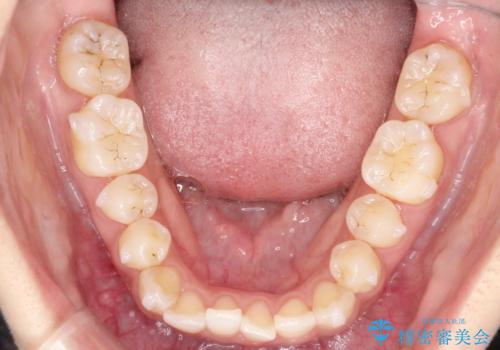

- 前歯の凸凹を主訴に来院された患者様です。

カウンセリング時に、側切歯が矮小歯であることを指摘したところ、適切な幅径での修復を希望されました。

インビザラインを用い、計画通りに歯並びを改善することができました。

矮小歯の幅径を大きくすることで、より理想的な噛み合わせを作ることができます。